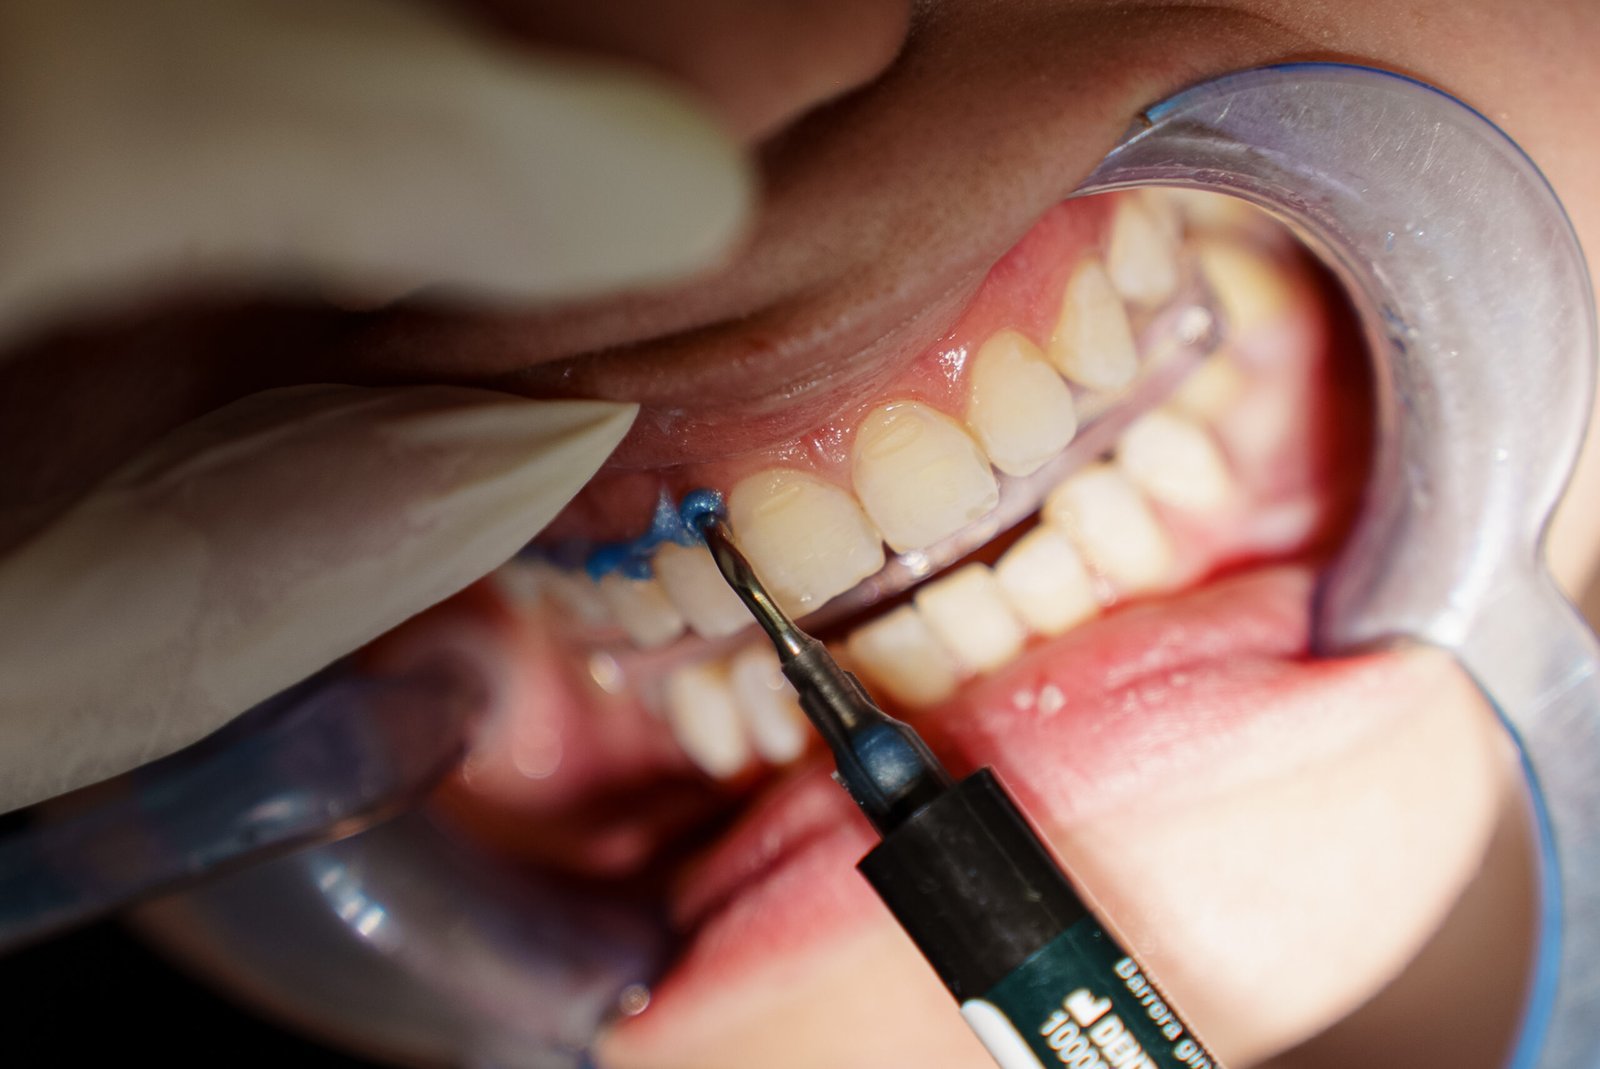

Screenshot